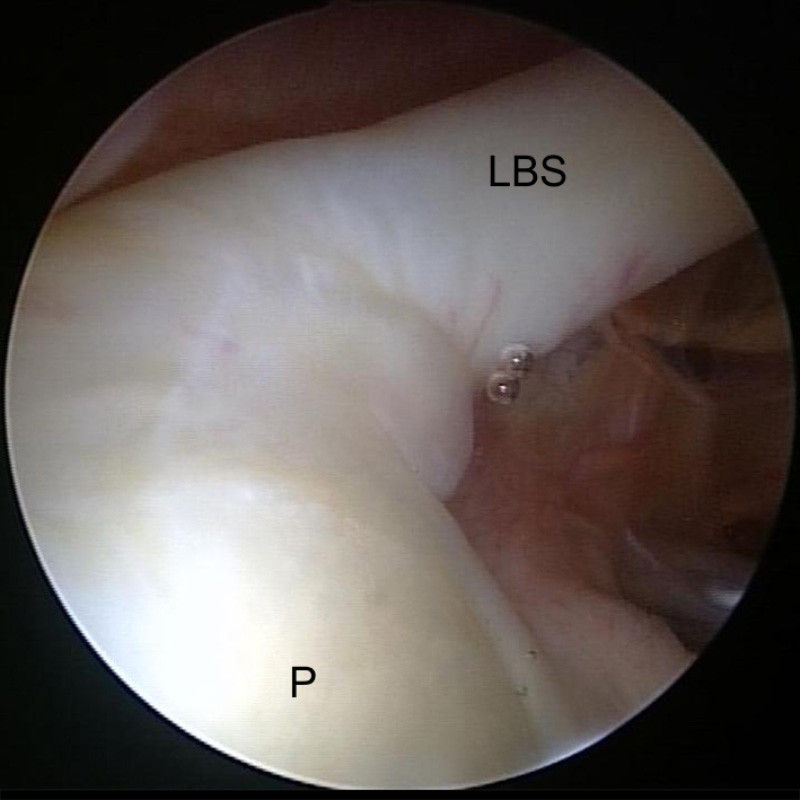

Gesunde Schulter mit normalem Abgang

Gesunde Schulter mit normalem Abgang der langen Bizepssehne (LBS) von der Pfanne (P)

Sie umschließen teilweise den Ausgang der Bizepssehne aus dem Gelenk und bilden zusammen mit einigen Verstärkungsbändern den sogenannten Bizeps-Pulley. Dieser stabilisiert die lange Bizepssehne.

Der sogenannte Bizeps-Pulley: Die lange Bizepssehne (LBS) gleitet über den Oberarmkopf (K)  aus den Gelenk zum Arm hinunter. Die Sehnen der Rotatorenmanschetten-Muskeln Supraspinatus (SSP) und Subscapularis (SSC) stabilisieren zusammen mit einem Band (SGHL) den Verlauf der LBS.